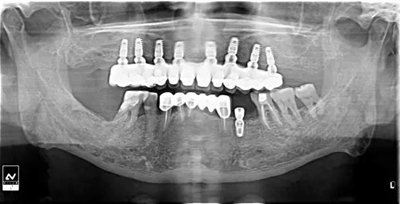

牙列缺失患者由于支持、固位、穩(wěn)定不足導(dǎo)致義齒效果差,如果在牙槽嵴內(nèi)植入種植體,種植體可以根據(jù)種植體數(shù)量不同提供義齒不同程度的固位、穩(wěn)定、支持,獲得不同的修復(fù)效果。當(dāng)單頜牙列缺失患者使用1-2顆植體,植體和覆蓋義齒之間可以靠一些附著體如磁性附著體、桿卡式附著體、球帽式附著體等裝置連接,主要提供固位和穩(wěn)定作用,少量的支持作用,當(dāng)單頜牙列缺失使用4顆植體時(shí),很大部分支持力可以由植體承擔(dān),當(dāng)使用4顆以上植體時(shí)可完全由種植體提供義齒的支持、固位和穩(wěn)定,甚至制作為不可摘戴的全口固定種植義齒。

1、種植固定修復(fù)后,義齒的基托面積大大減小,從而大大提升了患者的舒適度,同時(shí)惡心、發(fā)音障礙也大大減輕;

2、種植固定修復(fù)采取的是種植體支撐,或者種植體+粘膜支撐的受力方式,咀嚼效率比全口義齒提升很多,通俗來講,也就是老年人基本可以正常進(jìn)食,有利于老年生活的豐富和身體機(jī)能的保持;

3、種植固定修復(fù)因?yàn)橛蟹N植體的支撐,可以在一定程度上延緩牙槽骨的骨吸收,從而使義齒的使用年限更長;

當(dāng)然,說到種植固定修復(fù)的缺點(diǎn),除了可能出現(xiàn)的部分并發(fā)癥以外,不能不提的就是種植固定修復(fù)的價(jià)格,雖然遠(yuǎn)沒到某教授講到的一口牙等于一輛寶馬那種情況,但總體金額比全口義齒確實(shí)要高很多。即使是種植固定修復(fù)也會(huì)有不同的修復(fù)方案,金額差距還是比較大的。